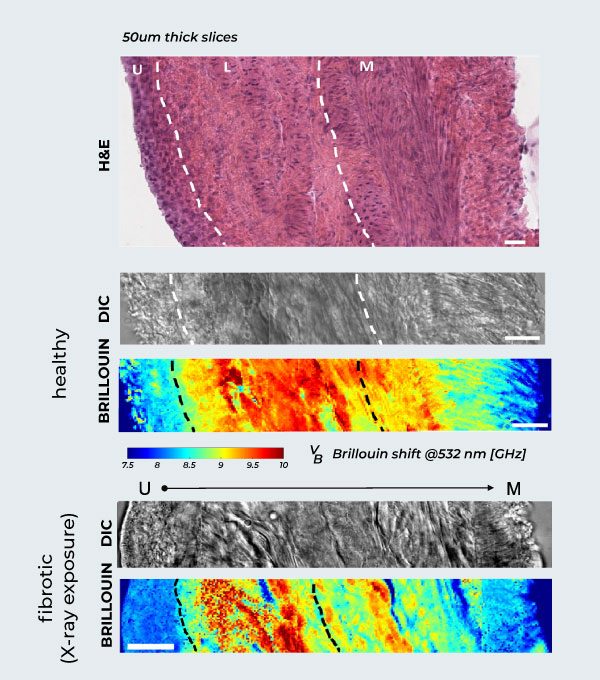

Brillouin Mapping of Radiation-Induced Actinic Cystitis.

Longitudinal evaluation of murine bladder walls following X-ray exposure. Healthy Tissue Anatomy: H&E (hematoxylin and eosin) staining of the healthy rat bladder wall, showing the different anatomical layers, alongside DIC and corresponding Brillouin maps from urothelium (left) to muscle (right). Biomechanical Progression: Correlative DIC and label-free Brillouin shift maps detailing fibrosis across the bladder wall layers (urothelium, lamina propria, muscle) at 2 months post-irradiation, compared to the healthy tissue above. Scale bars: 20 µm.

Adapted from: Martinez-Vidal, L., Testi, C., Pontecorvo, E. et al. Progressive alteration of murine bladder elasticity in actinic cystitis detected by Brillouin microscopy. Sci Rep 14, 484 (2024). https://doi.org/10.1038/s41598-023-51006-2